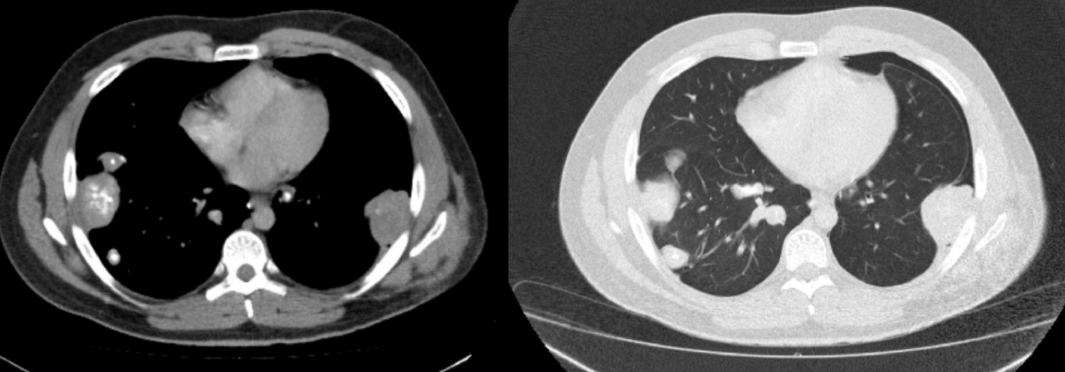

Lacher de Ballon

- Carcinome Rénal ++

Cannonball en anglais

Distribution vasculaire = Prédominent aux plages inf.

Distribution vasculaire = Prédominent aux plages inf.